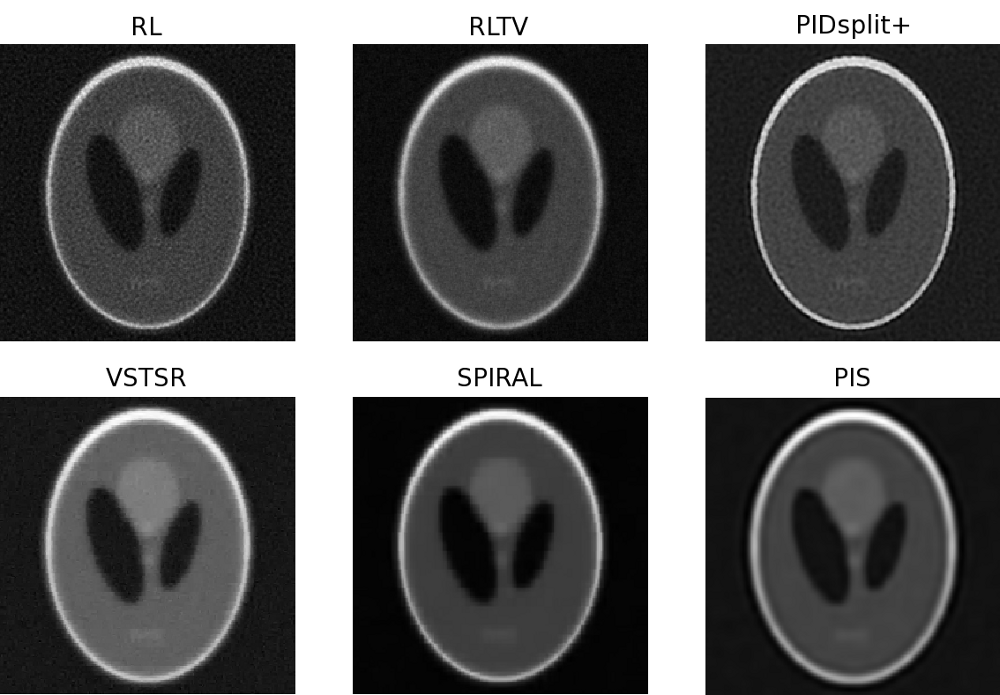

In this subsection, image reconstructions produced by the proposed and reference methods are tested using a microscopic image of glomerulus and the standard Shepp-Logan phantom, which are shown in Subplots A of Fig. 4 and Fig. 5, respectively. Similar to the case of sparse reconstruction, the images have been offset by a constant (background) value to give rise to different values of SNR. In particular, the value was adjusted to result in SNR equal to 32 (moderate noises) and 8 (strong noises). The original, blurred, and contaminated images of the glomerulus and Shepp-Logan phantom are summarized in Fig. 4 and Fig. 5 for all the tested values of and SNR.

For the case of glomerulus, the reconstructions obtained with the proposed and reference methods are summarized in Fig. 6 (for , SNR=32) and Fig.7 (for , SNR=8). Moreover, Fig. 8 and Fig. 9 depict the reconstructions of the Shepp-Logan phantom for the cases of , SNR=32 and , SNR=8, respectively. Analyzing these results, one can clearly see that, in all the above cases, the PIS algorithm yields reconstructions of superior quality (in terms of the resolution and contrast gain), as compared to the reference methods. This observation is further supported by the quantitative measures of Tables III and IV, which compare the estimation results in terms of the NMSE, SSIM index, and the number of iterations. As evidenced by the tables, the PIS method produces the lowest NMSE and the largest SSIM index among all the methods under comparison. As to the number of iterations required by PIS, one can see (with a reference to Table II) that the method has a computational complexity either comparable or lower than that of the reference methods.